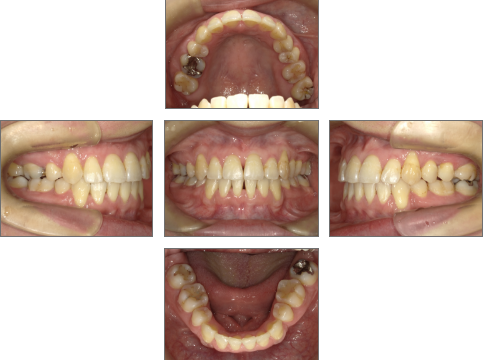

【治療後】

今回の症例は30代で治療を開始し、約2年で治療を終了した例です。

●主訴

歯並びのガタガタが気になる。歯磨きがしづらく、将来、歯が悪くなってしまうのではないか、心配。

●診断名あるいは主な症状

叢生

●治療期間

約2年